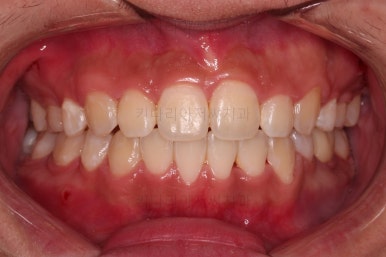

초진 시 입안의 모습입니다.

앞니가 많이 삐뚤고, 송곳니가 부각되어 덧니처럼 보이네요.

종료 시의 사진들을 전후 비교해 보겠습니다.

입매가 좋아졌고 입을 다무는 편안함도 좋아졌으며 치열이 가지런해졌으며 웃을 때 보이는 치열의 느낌도 좋고 교합도 잘 마무리 되었네요.